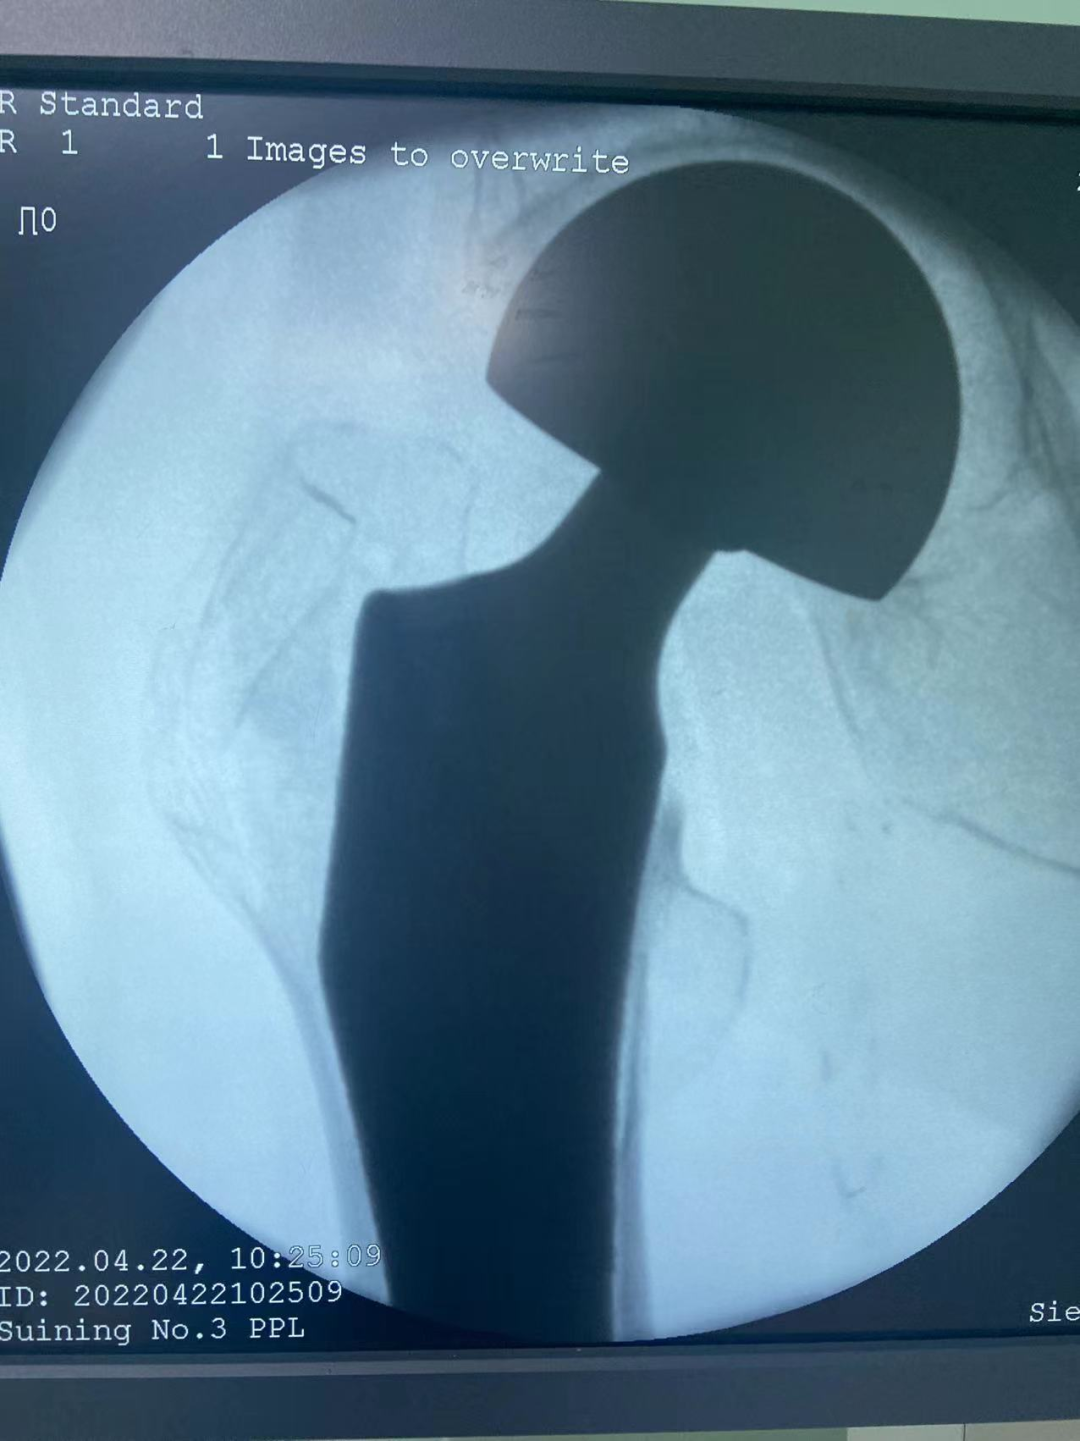

4月22日上午,历经30分钟,我院成功实施第一例执行国家集采人工关节置换手术,费用由之前的2.3万元左右降到7000元左右,患者为它付费少七成。

79岁何奶奶,因扭伤后出现右髋部疼痛伴活动受限3天入院,诊断为右股骨颈骨折、骨质疏松症,需要手术治疗,结合患者的基础疾病及年龄,经与患者及家属沟通,我院骨伤科团队决定为她实施人工股骨头置换术,恰好赶上国家政策—人工关节集中采购,人工关节降价!4月22日上午,由骨伤科周建全主任主刀,历时30分钟完成手术,术中失血仅50ml!

该名患者成为我院执行国家人工关节集中带量采购落地的首位获益患者,手术耗材费用仅7000元,比过去节省近70%,约1.6万元。耗材费用大幅降低成为关节伤患者的重大福音,进一步减轻了患者的就医负担。